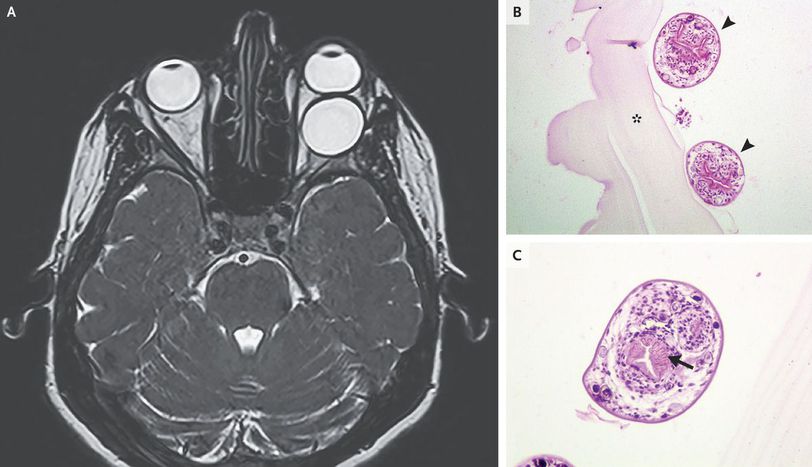

A 31-year-old woman presented to the emergency department with a history of blurred vision in the left eye over a 4-week period and progressive bulging of the left eye over a 2-week period. Physical examination revealed nontender proptosis of the left eye, paresis of the left abducens nerve, and reduced visual acuity in the left eye. A T2-weighted gadolinium-enhanced magnetic resonance image of the brain showed a well-defined, ovoid, cystic, and retrobulbar lesion in the left orbital cavity (Panel A). The optic nerve was displaced nasally and the lateral rectus muscle was compressed. The patient underwent left lateral orbitotomy, and the cyst was completely removed but ruptured during surgery. The area was washed with saline. Histopathological examination revealed multiple protoscolices (Panel B, arrowheads), with central hooklets (Panel C, arrow), adjacent or attached to a thick, acellular laminated echinococcal cyst membrane (Panel B, asterisk). A diagnosis of a hydatid cyst caused by the Echinococcus granulosus tapeworm was made. Thoracic and abdominal computed tomographic scans revealed no extraorbital organ involvement. The patient received a 3-month course of albendazole, and at follow-up 3 months later, she had full recovery of visual acuity.